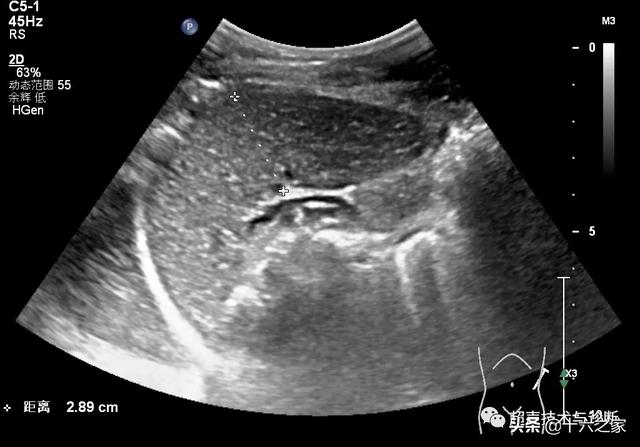

脾厚度的测量▲脾长径:测量脾上极最高点至下极最低点的距离脾长度的

【超声微课堂】脾脏超声诊断